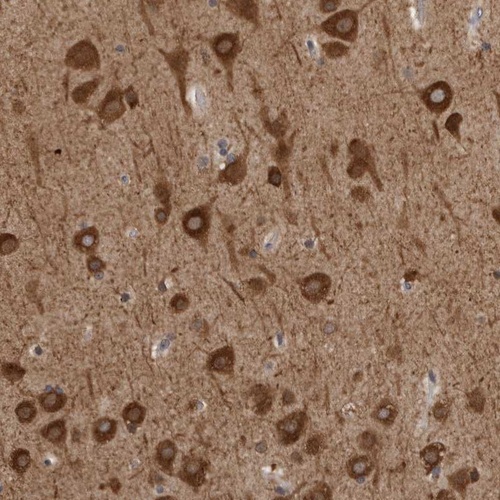

Immunohistochemical staining of human cerebral cortex shows strong cytoplasmic positivity in neuronal cells.